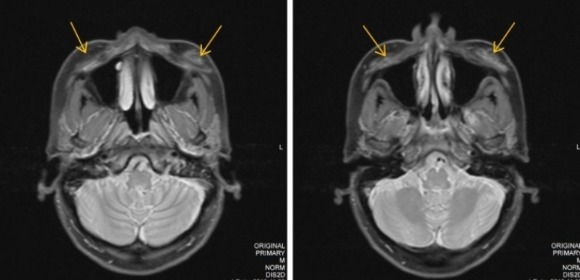

MRI臨床影像(上圖)亦證實,再生針注射後2.5年,無任何殘留訊息,不會形成骨頭組織,也不會遮蔽X光,僅有組織結構增厚的改善結果。臨床指出,再生針效果約12到18個月。《Pavicic T. et al., 2013》

再生針並非源自人體或動物組織,降低了病原體污染的風險。根據《Clinical, Cosmetic and Investigational Dermatology》MRI證實,注射後2.5年,看不到任何CaHA微晶殘留,組織體積仍維持增加,顯示填充材質被代謝,且肌膚經過再生針刺激所生成的新膠原仍能提供結構支撐,使臉部線條自然立體。